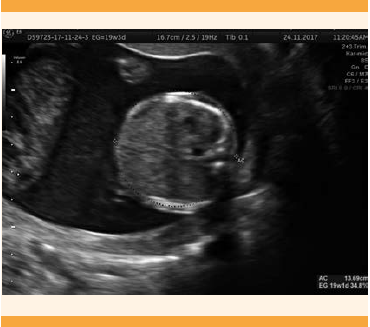

Paciente de 21 años, primigesta, sin antecedentes personales patológicos. Sin control prenatal en el primer trimestre. El primer ultrasonido reportó embarazo gemelar monoamniótico, monocorial, de 26.2 semanas de gestación. El gemelo A vivo, con placenta corporal anterior grado 0, líquido amniótico aumentado. El gemelo B acéfalo, con malformaciones en la columna vertebral y extremidades. La valoración de los especialistas en medicina materno fetal reportó: embarazo gemelar monocorial, monoamniótico, de 25 semanas de gestación. Feto A con fetometría promedio 3 semanas mayor a la amenorrea. Revisión limitada del feto B, con polihidramnios, bradiarritmia con pausas largas o periodos de asistolia.4,5,6 El feto B sin observación de la cabeza o las extremidades completas, con edema sin distinguirse el corazón. Diagnóstico: feto acárdico. La consulta con el Instituto Nacional de Perinatología reportó: gemelo B acárdico, acéfalo, flujo por arteria umbilical, con 25.5 semanas de gestación por fetometría, peso: 916 ± 134 g. Hemodinamia normal, situs solitus, levocardia, y levoápex, cavidades cardiacas simétricas, tabique interventricular, concordancia aurículo-ventrículo y ventrículo-arterial. Líquido amniótico aumentado. A las 26.2 semanas de gestación el feto A pesó aproximadamente 901 g. La flujometría de la arteria, vena, ducto venoso y cerebral media se reportó sin alteraciones aparentes, ritmo sinusal. A las 29.1 semanas de gestación el feto A se estimó con peso de 1462 ± 213 g, peso por debajo del promedio, Chamberlain de 7.14 cm. El gemelo B, acárdico, con volumen estimado de 1043 cc, flujo del cordón no valorable por posición de los fetos. El último ultrasonido reportó: embarazo de 31.1 semanas. Feto A con peso de 1736 ± 253 g, presentación pélvica, con aplanamiento en la curva de crecimiento, sin datos de hidrops ni insuficiencia cardiaca. El nacimiento fue por cesárea en el Instituto Nacional de Perinatología del gemelo A vivo, de sexo masculino, peso 1844 g, talla 45 cm, Apgar 8-9, Capurro de 36 semanas de gestación (Figuras 4-7), gemelo B acárdico, de 25 x 20 g, peso 2148 g (Figuras 8 y 9). La paciente fue dada de alta del hospital con el gemelo vivo, sin complicaciones.

Figura 4 Caso 3: Ultrasonido pélvico de embarazo gemelar monocorial monoamniótico de 25 semanas de gestación con feto A indistinto, fetometría promedio 2 semanas y 2 días mayor a amenorea y polihidramnios.